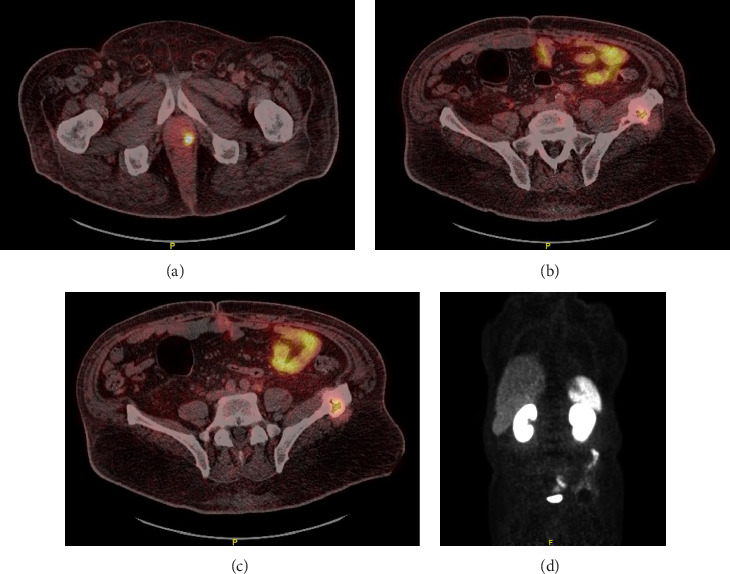

Polyneuropathy, organomegaly, endocrinopathy, monoclonal gammopathy, and skin change (POEMS) syndrome is a multisystem disorder, and it is often misdiagnosed with other entities including chronic inflammatory demyelinating polyneuropathy (CIDP). Here, we present a case of a patient with presumed metastatic prostate cancer due to prostate-specific membrane antigen (PSMA) avid lesions and a history of neuropathy not responding to conventional treatment for CIDP. His physical exam findings, in addition to an appropriate workup, led to a diagnosis of POEMS syndrome. This case highlights the importance of a high index of clinical suspicion, even when imaging suggests otherwise.